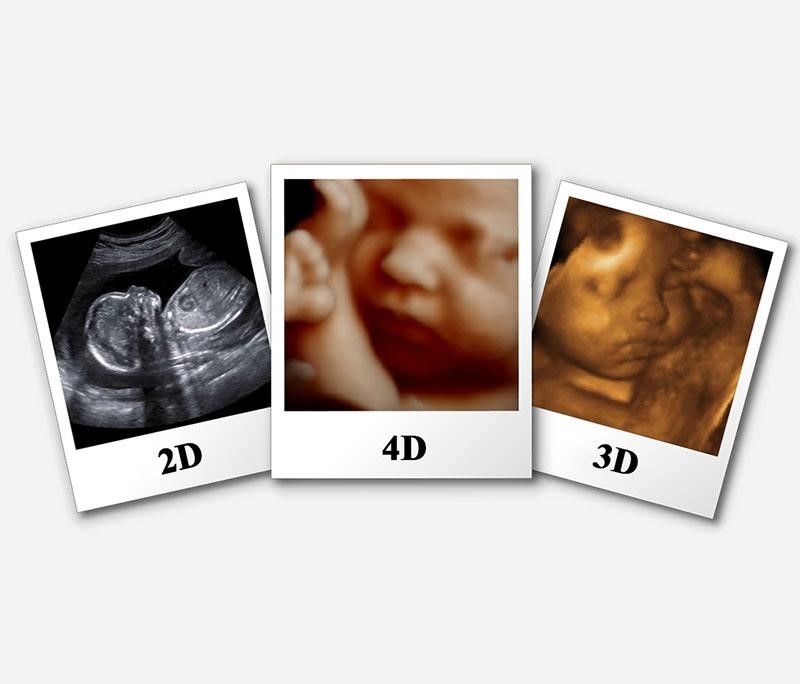

Siêu âm 3D giống với siêu âm 2D ở chỗ đều là siêu âm ba chiều. Nhưng siêu âm 3D cho kết quả là hình ảnh màuc, có kích thước lớn hơn, rõ hơn, tái hiện hình ảnh chân thực hơn siêu âm 2D rất nhiều.